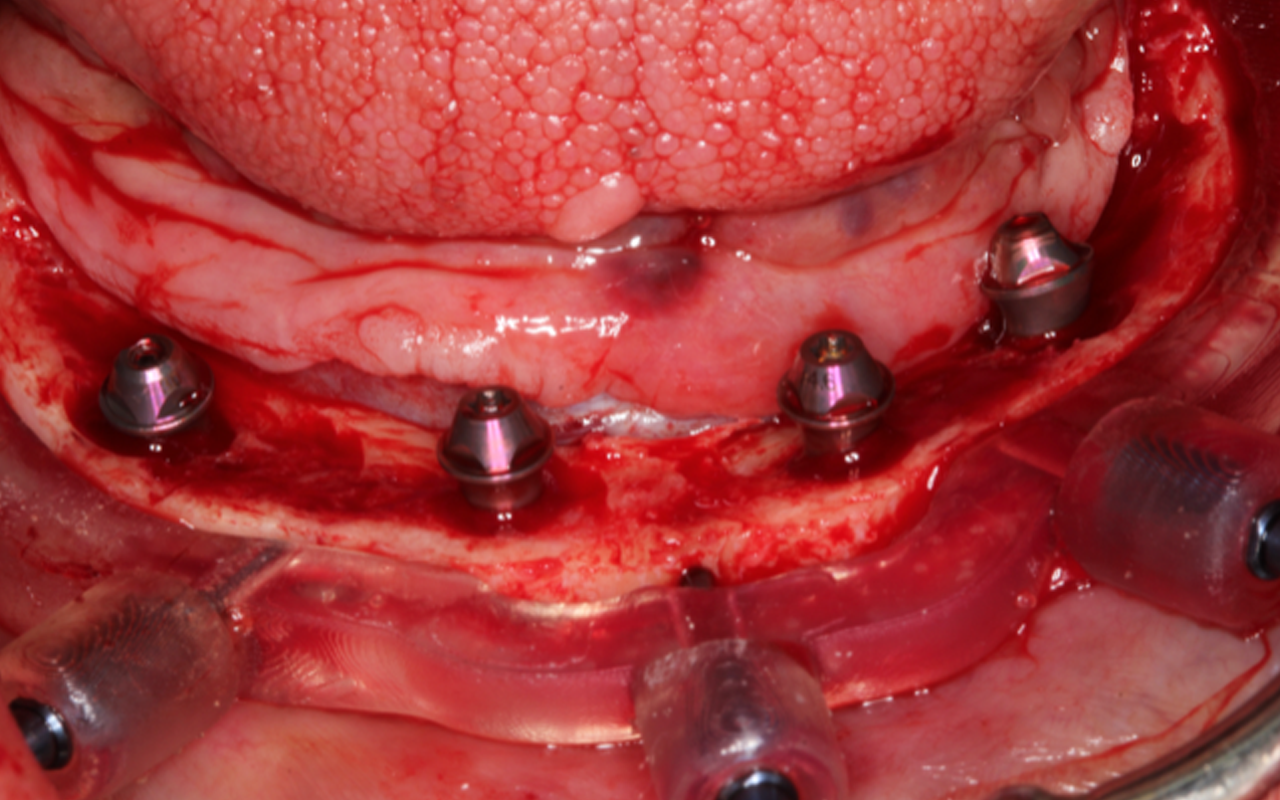

Patient treatment by faculty will focus on advanced surgical treatment with implant placement and GBR/soft tissue grafting in the anterior esthetic zone.

Full arch patient surgery with 3D surgical and stackable guides, implant scanning protocols with 3Shape and photogrammetry with PIC scanner and delivery of 3D printed full-arch provisionals.